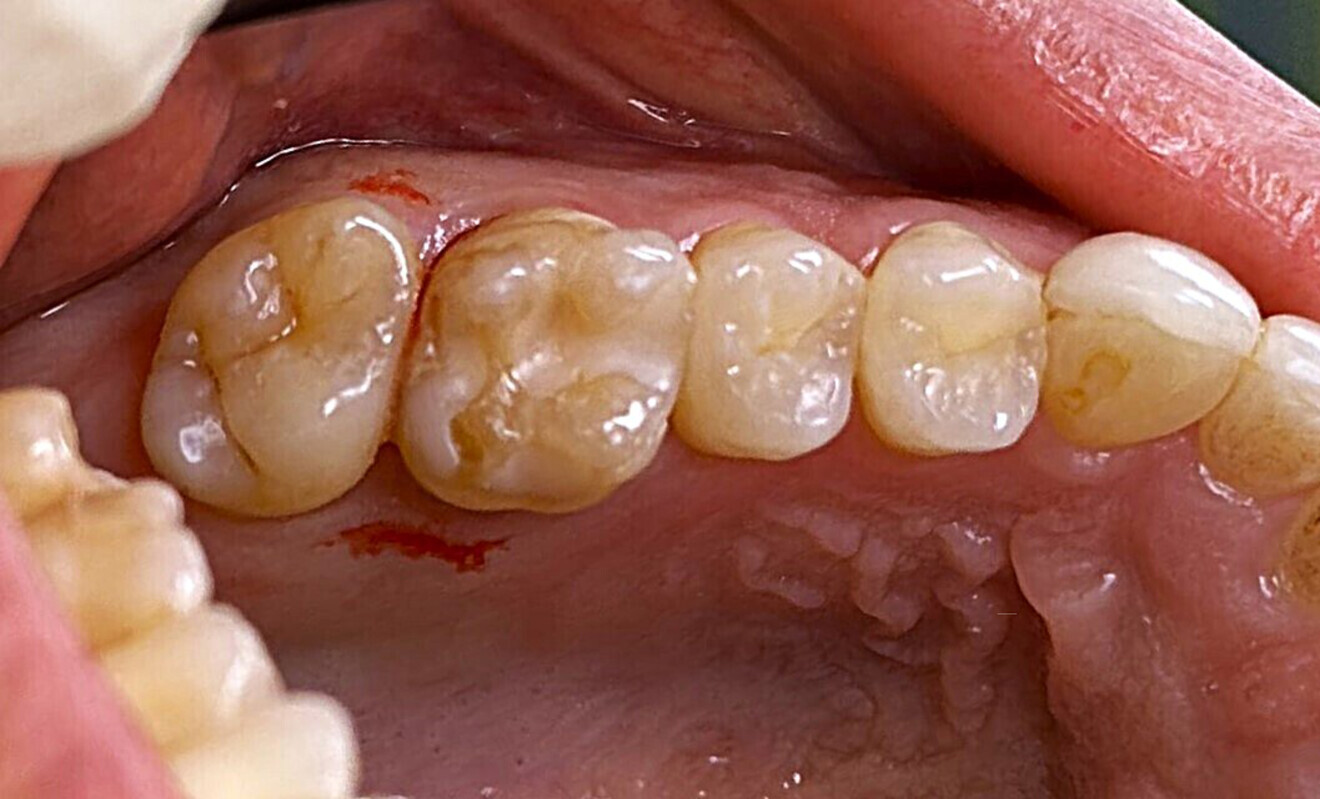

A 23-year-old female patient presented with cold sensitivity of the teeth in the maxillary right posterior sextant. Examination noted old composite fillings in the molars and premolars and recurrent caries on each tooth (Fig. 19). A bitewing radiograph was taken to evaluate the extent of the recurrent caries and the dimensions of the composite restorations (Fig. 20). Owing to the dimensions of the restorations and caries, inlay and onlay restorations were suggested to restore the teeth and preserve tooth structure as an alternative to complete crowns. The patient’s questions were answered, and she agreed to the proposed treatment. She was informed that the treatment could be completed in a single appointment utilising 3D printing for restoration fabrication. Time in the schedule permitted treatment to be performed during that same appointment. Our intent is to provide conservative restoration with superior accuracy and definition compared with milling, as well as better predictability and mechanical properties compared with direct resin composite restorations.

Fig. 19: Clinical view of the old composite restorations with recurrent caries on the molars and premolars.